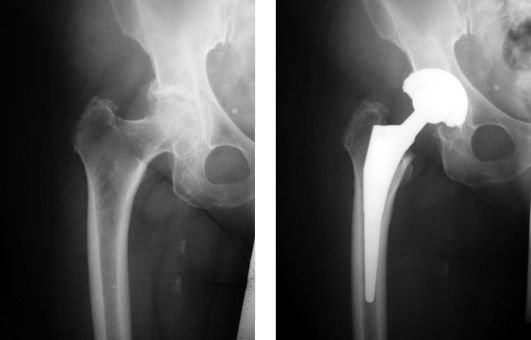

The company ORTHOPEDIC NIKIFOROV was founded in 1998 by the candidate of medical sciences. doctor of orthopedic-traumatologist of the highest category Nikiforov IA Owing to high professionalism and results of work, ORTONIC has gained well-deserved reputation and reputation among colleagues and population of Dnepropetrovsk region and CIS countries (Russia, Moldova, Armenia, etc.). The principle of the enterprise is NO IMPOSSIBLE, it is based on knowledge, experience and active implementation of modern technologies in orthopedics and traumatology. Conservative methods of treatment include individual selection of medicines, therapeutic blockades, manual therapy, massage, physiotherapy (vibration table, magnetotherapy, bioptron, electromyostimulation, etc.), rehabilitation with the suggestion of the necessary concomitant devices and means for the fastest recovery (corsets, bandages, various joint fixators, crutches, walking sticks, etc.). Various minor invasive interventions (chymonucleolysis, vertebroplasty, kyphoplasty, percutaneous nucleoplasty using cold plasma) that are performed on an outpatient basis are successfully used to treat problems associated with spine pathology. The latest modern treatment methods introduced in our company are endoscopic operations using the TYSSES technique of Joimax (Germany) with intervertebral hernias, stenosis and other pathologies of the spine, which allow to avoid complications occurring during open operations and the accompanying general anesthesia. We have many years of successful experience in traditional and modern minimally invasive endoprosthetics of large and small joints, which remains the main direction of our activity. Our company is the exclusive representative of the German company IO International Orthopaedics Holding GmbH, which based on the already known prostheses, its ideas and technological capabilities, has developed and implemented a new concept in hip replacement - an artificial joint prosthesis (ICON). We assist interested colleagues in training the operative technique for installing an artificial joint prosthesis - ICON, both in the workplace and in Germany. For 20 years we have been successfully cooperating with Sanitatshaus Gerd Klinz ortho team, an enterprise that for 20 years has been one of the leading places in Germany for the production of functional prostheses of the upper and lower limbs, as well as cosmetic prostheses of limbs and other body parts (nose, ears, eyeballs, fingers). We have an atmosphere of friendliness and human participation. Politeness, benevolence, the desire to understand and help is the basis of our attitude towards patients. We are always glad to see you and will do our best to make you feel great! We are waiting for you at: Ukraine, Dnepr, Gagarin Ave., 13 (under reconstruction) on all questions to address: tel .: +38 (050) 488-88-92 E-mail: orthonik.ukr@gmail.com Germany, Spine Nano Klinik, Zeppelinstr. 21, Potsdam Tel. +4901801121919 E-mail: kmw.nikiforov@hotmail.de